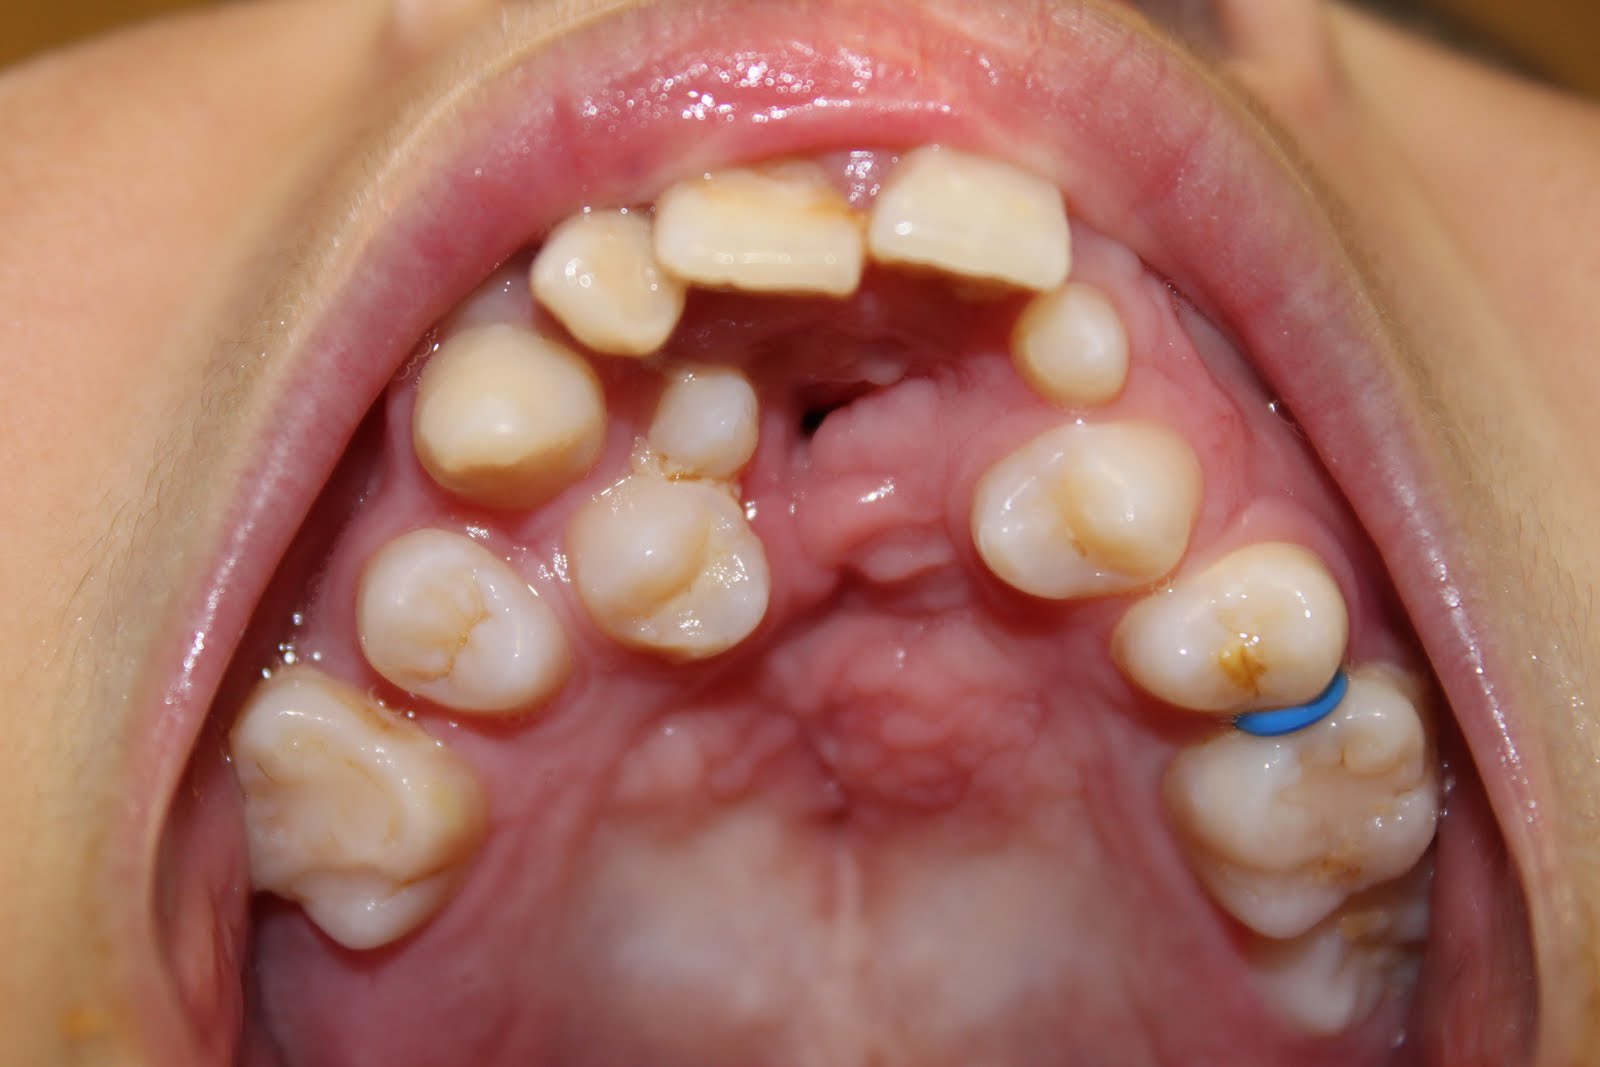

Easy Dentistry sinus & fistula SINUS & FISTULA DESCRIPTION IN Pinhole Fistula what is a vaginal fistula? Vvf is an abnormal fistulous tract. when doing the dye test, it is easy to miss a pinhole fistula of the urethra as the foley catheter may be against the fistula. (3.1) small and pinhole fistulas. A cause of persistent incontinence from a kock pouch. a rectovaginal fistula is an epithelialized. Pinhole Fistula.